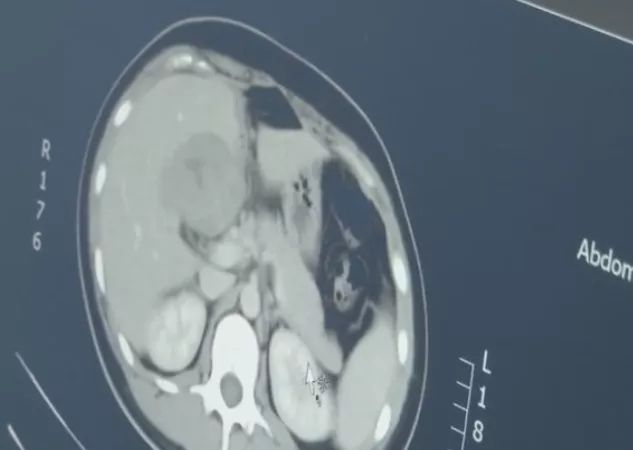

在尤女士的肝脏部位发现了一个包块

而这个包块竟是一个胚胎!

却没想到CT检查后发现

胚胎跑到了肝脏的位置

这是一种罕见的宫外孕